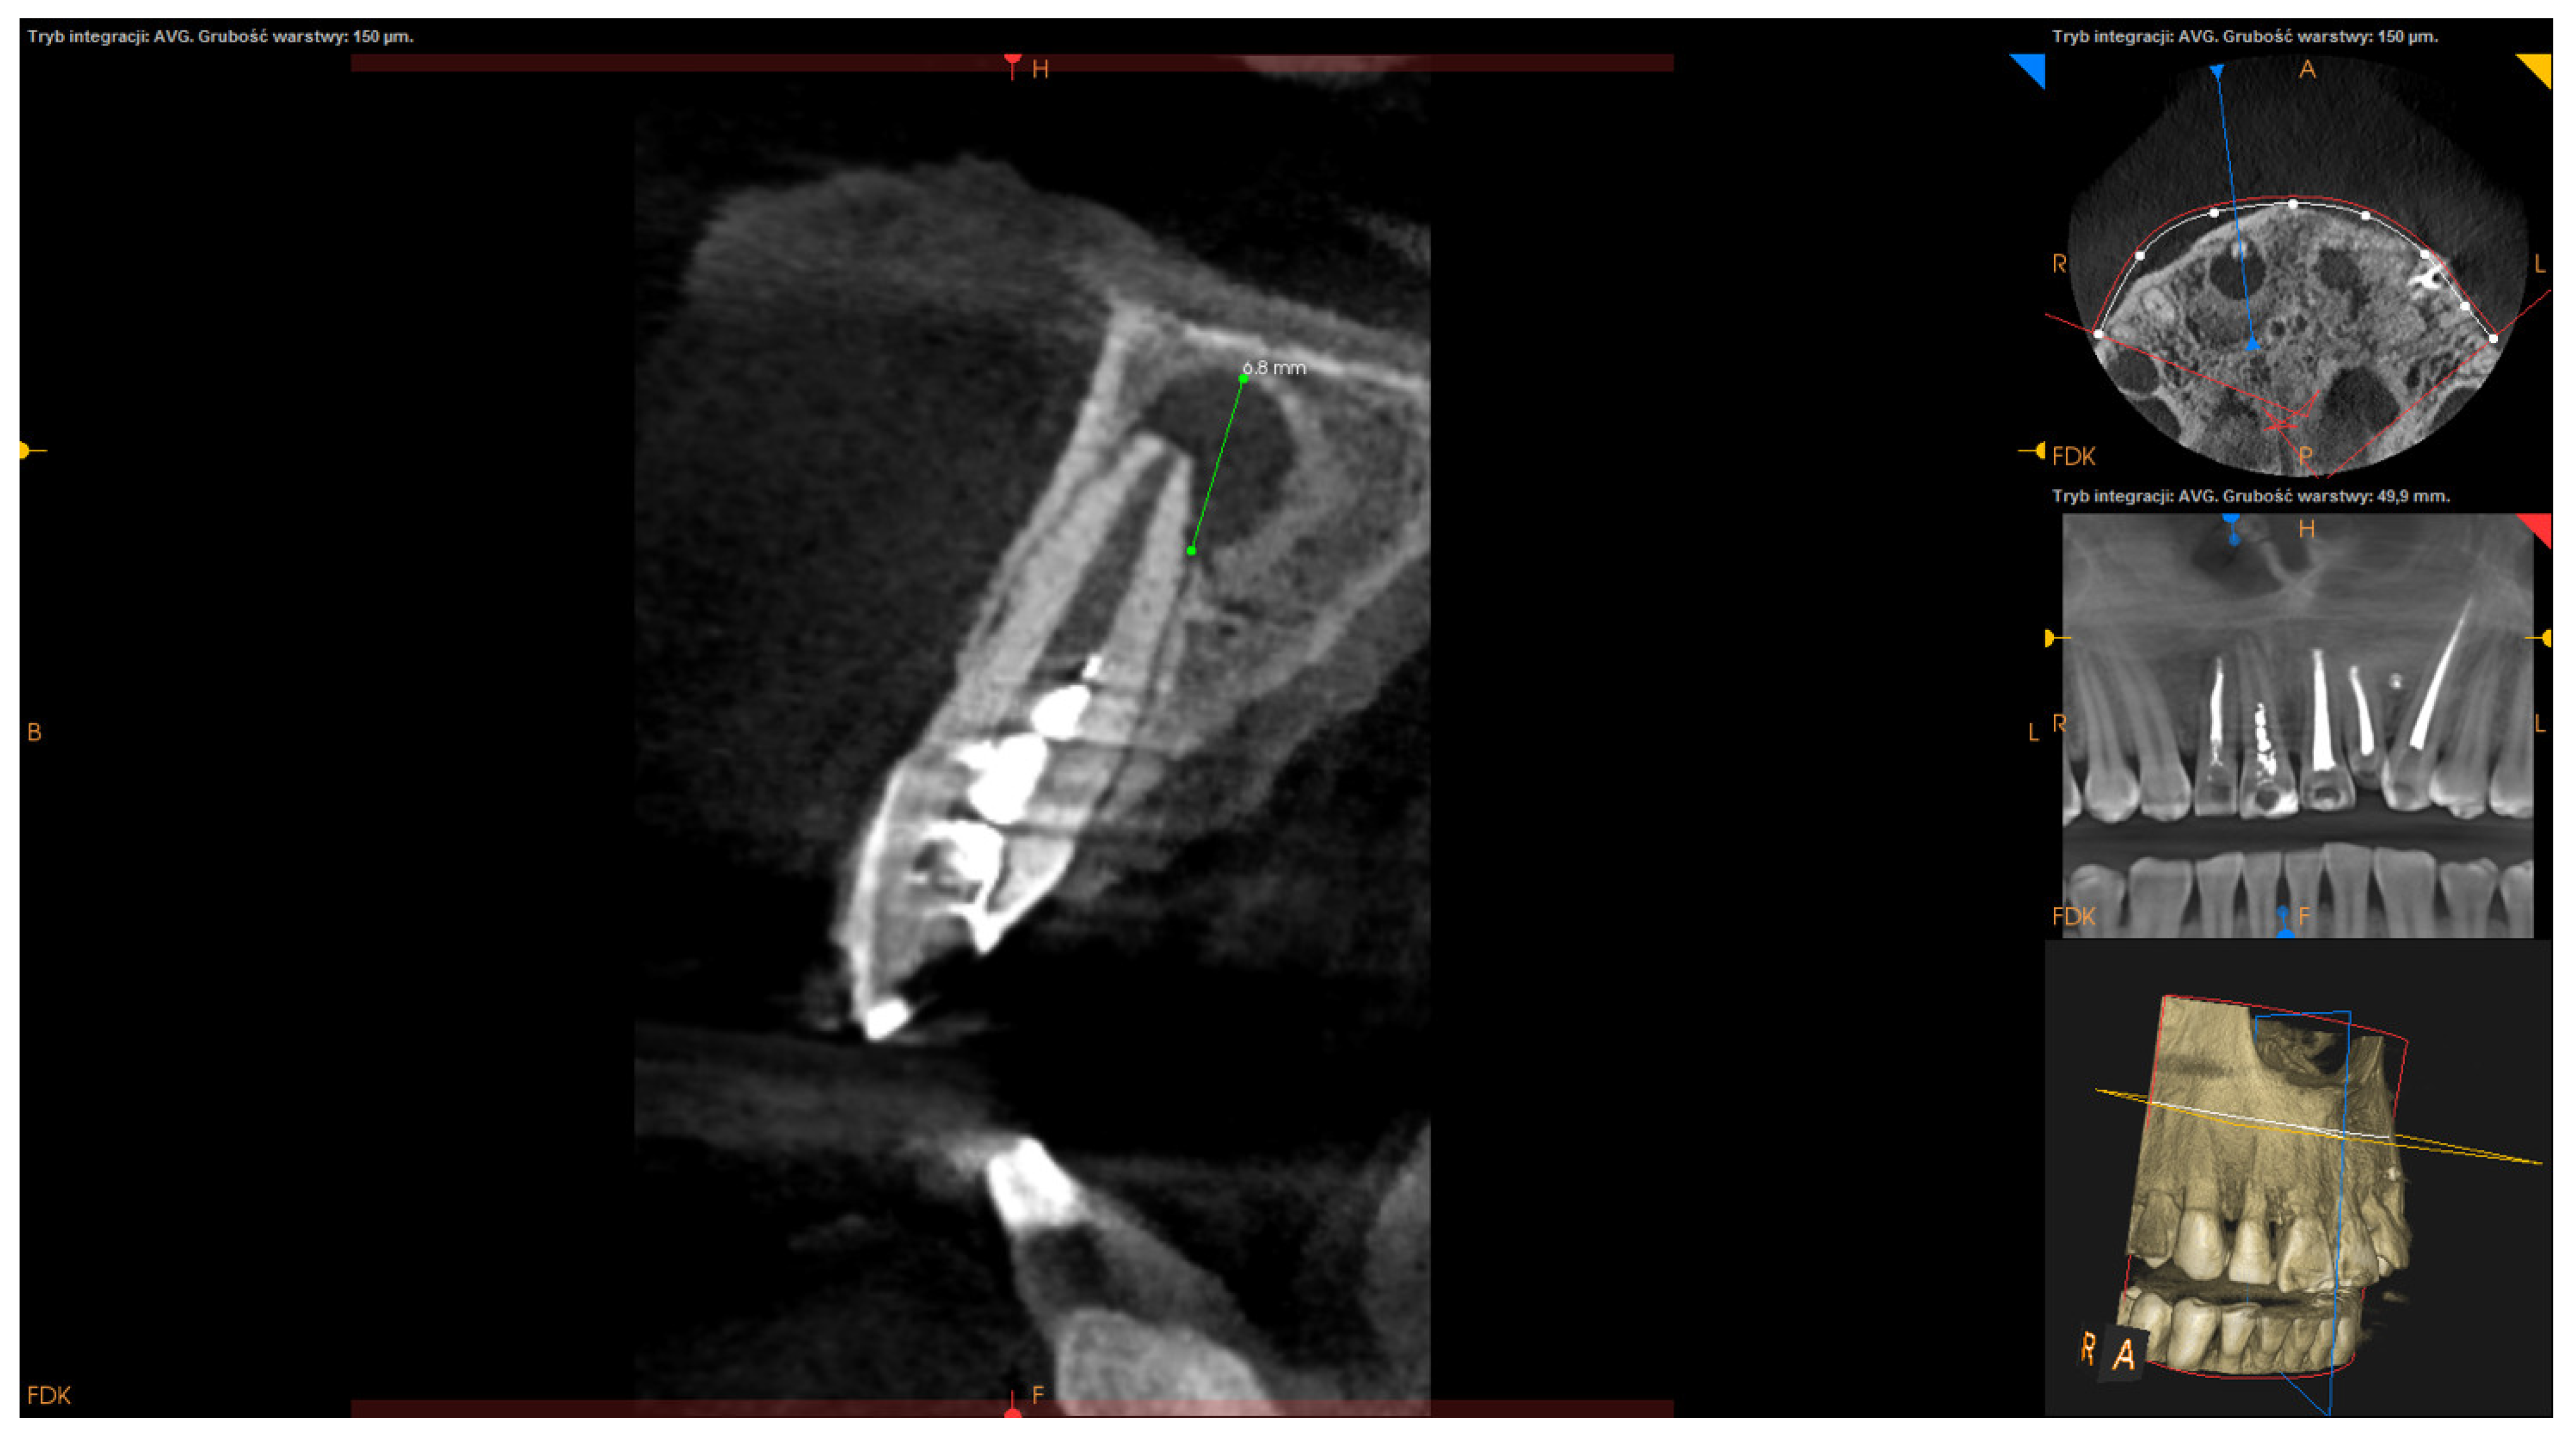

- Apicocoronal maximum diameter (measured in the sagittal section) (Figure 2);

| apicocoronal maximum diameter M ± SD: 8.93 ± 3.71 | <8.93 mm | 48 (53.93%) |

| >8.93 mm | 41 (46.07%) | |